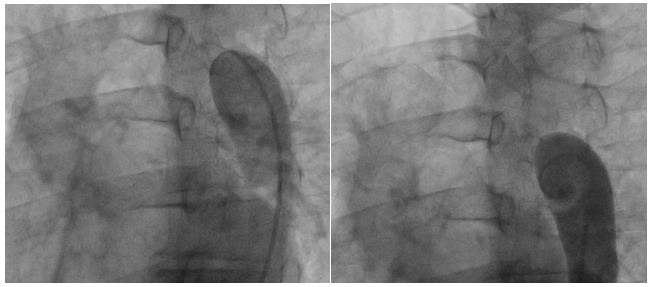

Femoral access cardiac catheterization showed complete occlusion of the thoracic descendent aorta distal to the left subclavian artery, without passage of the wire through the occlusion zone and with an 85 mm Hg gradient (Fig. 1A and 1B). Radial access cardiac catheterization showed significant proximal stenosis of the left anterior descending artery, circumflex artery, and right coronary artery.

Figure 1A and 1B: Thoracic aortogram. Aortic occlusion is evident.